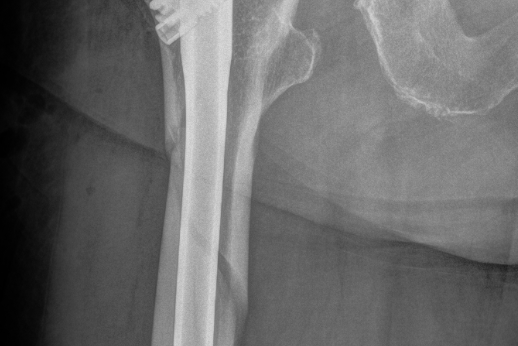

Figur 2 viser røntgenbilder av en hofte med artrose (figur 2a til venstre) og en hofte som har fått en sementert hofteprotese (figur 2b til høyre).

I prinsippet består en hofteprotese av en stamme som går ned i lårbenet, et hode som settes på toppen av stammen som erstatning for lårbenshodet, og en kunstig hofteskål (koppen) (figur 1). Forskjellige stammer kan kombineres med kopper av forskjellige merker, slik at kombinasjonsmulighetene blir svært mange.

Det er to hovedprinsipper for innfesting av protesedelene mot pasientens bein; enten med beinsement (polymetylmetakrylat) eller uten sement. Det er flere produsenter som lager beinsement. På begynnelsen av 1990-tallet ble Boneloc bensement brukt i Norge. Denne og to andre sementtyper viste seg å gi dårlige resultater, og disse sementtypene gikk ut av bruk for flere år siden.

De usementerte protesene er vanligvis laget av titanium og har enten en overflatestruktur eller et overflatebelegg som gjør at bein kan gro fast på protesen. Begge deler kan fungere godt i forhold til å få protesene til å sitte fast.